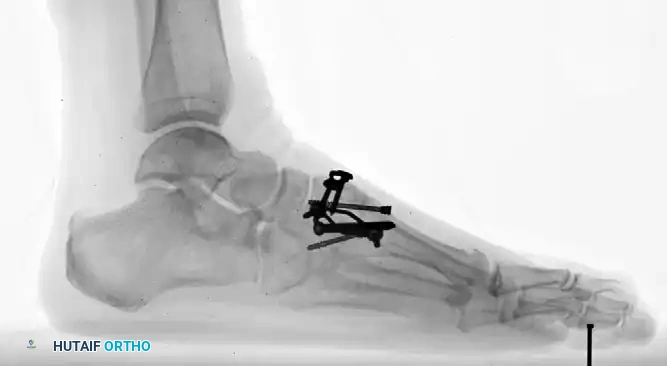

بعد التأكد من التصحيح المثالي وتطابق العظام باستخدام الأشعة، يتم التثبيت النهائي. تتوفر أشكال متعددة من التثبيت، وغالباً ما يُفضل استخدام براغي مجوفة بقطر 4.0 ملم بتقنية الشد لضمان انضغاط العظام معاً بقوة.

في بعض الأحيان، يتم استخدام شرائح معدنية ظهرية مصممة خصيصاً، أو شرائح داخلية لزيادة الاستقرار، وهو ما يتطلب تسليخاً دقيقاً ووضع الشريحة أسفل وتر الظنبوب الأمامي.

بالنسبة للبراغي التي تحتوي على رؤوس، يتم عمل تجويف صغير في العظم لدفن رأس البرغي، وذلك لتجنب كسر القشرة العظمية العلوية عند شد البرغي.